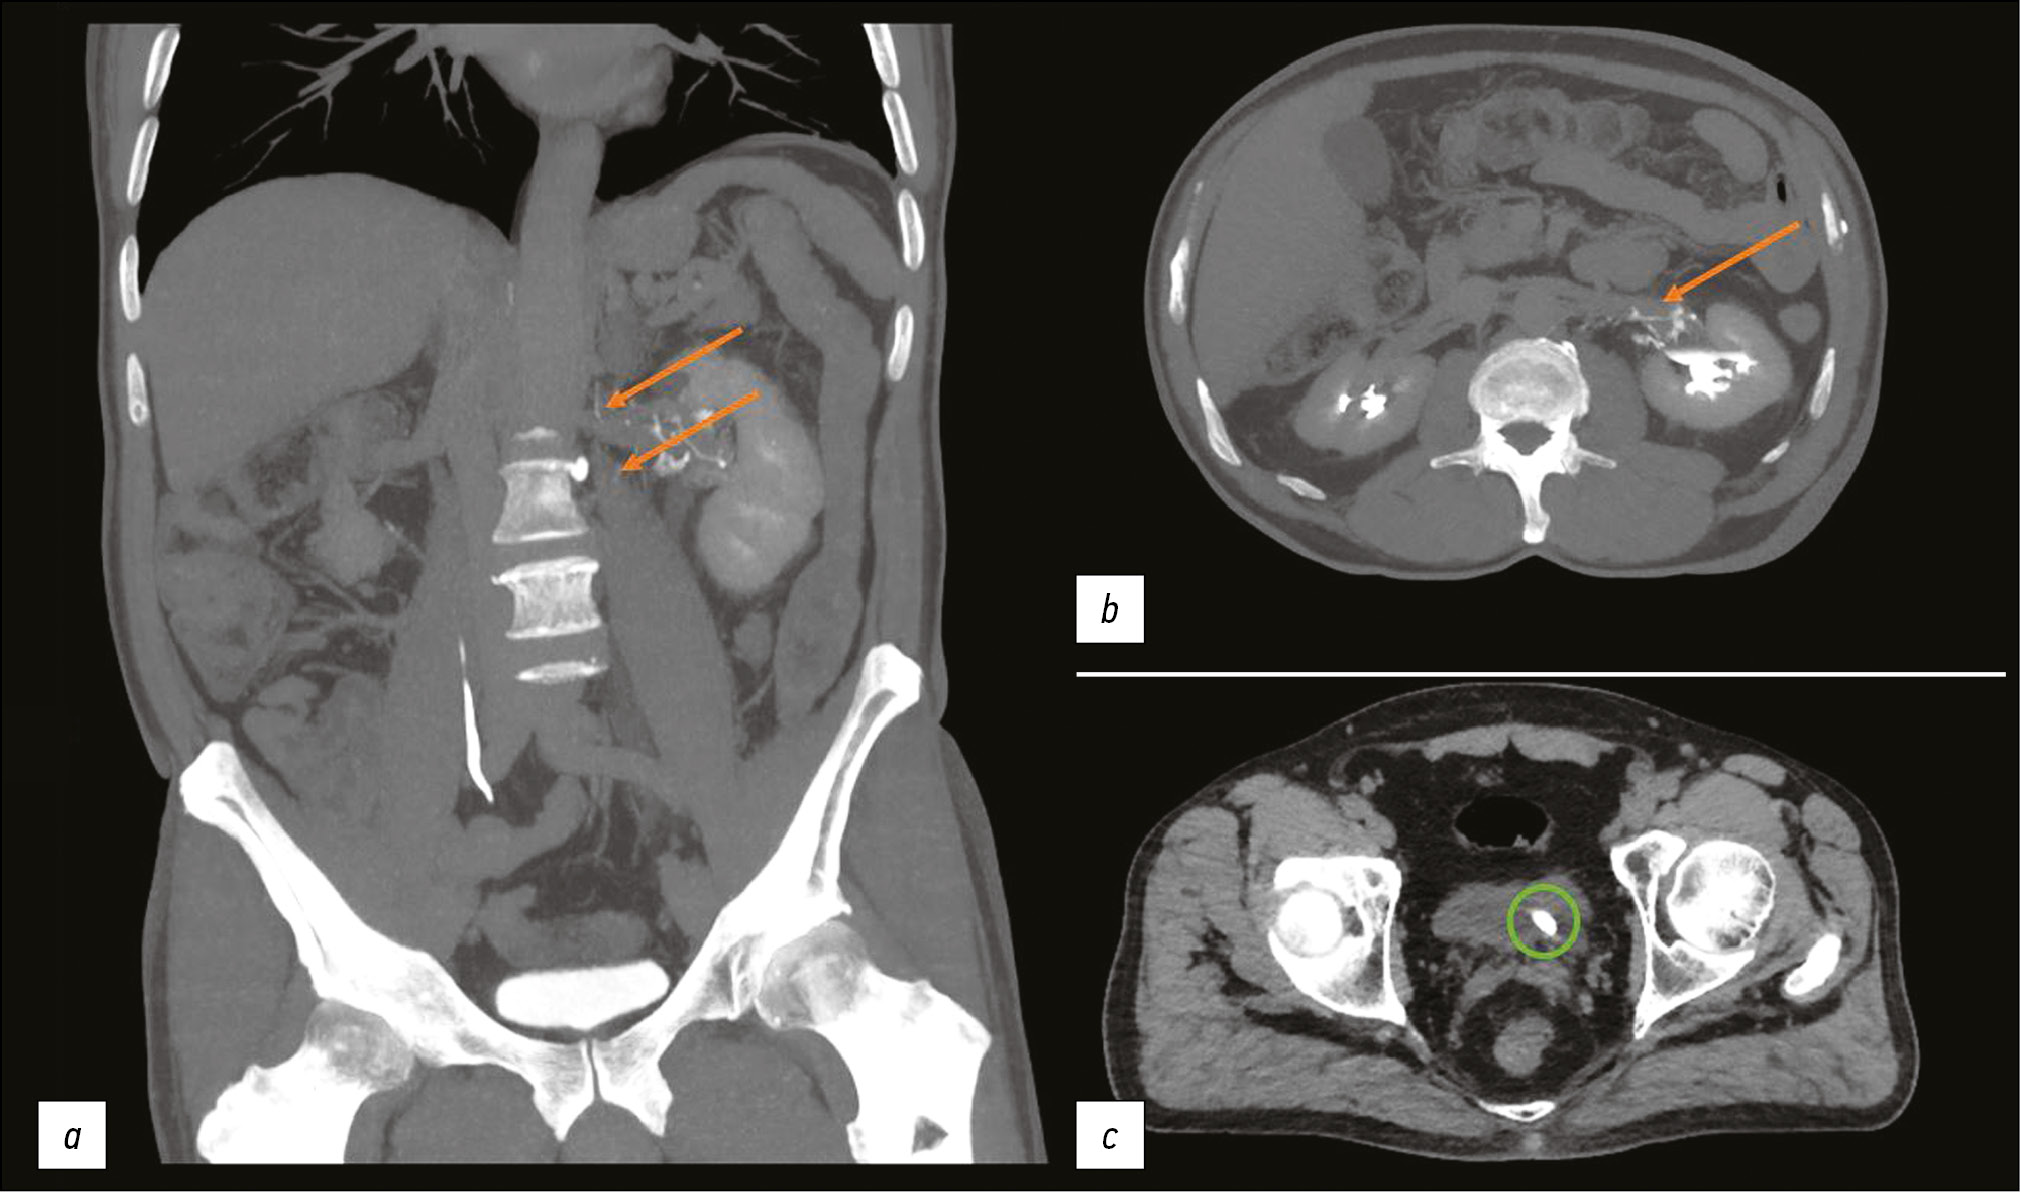

The CT showed a contrast extravasation in the left kidney lymphatic ductus up to the thoracic lymphatic duct (typical for ULF). A calculus at the left ureteric orifice with ureteropyelocalicectasis and signs of urinary tract obstruction, as well as a calculus at left middle calix, were found during the examination (Figure 2).

Fig. 2. Computed tomography of the abdomen with intravenous contrast enhancement. The excretory phase: (a, b) Orange arrows show the contrast spread along lymphatic vessels; (c) A green circle highlights a calculus at the left ureteric orifice.